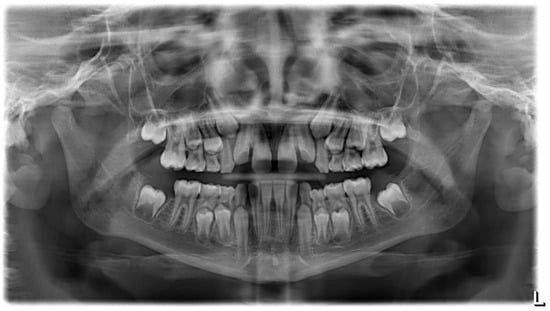

3.4. Clinical Case #4

| Cephalometric Analysis before Treatment | Val | Dev | Min | Med | Max | Diff |

|---|---|---|---|---|---|---|

| SNA | 74.5° | −xxx | 80° | 82° | 84° | 5.5° |

| SNB | 70.3° | −xxxx | 78° | 80° | 82° | 7.7° |

| ANB | 4.2° | x | 0° | 2° | 4° | 0.2° |

| sna-snp^Go-Gn | 30.7° | xx | 15° | 20° | 25° | 5.7° |

| S-N^sna-snp | 11.4° | N | 7° | 10° | 13° | 0° |

| S-N^PO | 25.2° | xxx | 11° | 14° | 17° | 8.2° |

| S-N^Go-Gn | 42.1° | xx | 27° | 32° | 37° | 5.1° |

| SNBa | 140.5° | xx | 124° | 129° | 134° | 6.5° |

| SND | 66.4° | −xxxx | 74° | 76° | 78° | 7.6° |

| IS^II | 120.3° | −x | 125° | 130° | 135° | 4.7° |

| IS:N-A | 1.9 | −xx | 3 | 4 | 5 | 1.1 |

| II:N-B | 2.2 | −x | 3 | 4 | 5 | 0.8 |

| II:A-Pog | 0.8 | N | −1 | 1 | 3 | 0 |

| Ls:Line S | 0.9 | N | −1 | 0 | 1 | 0 |

| Li:Line S | −0.8 | N | −1 | 0 | 1 | 0 |

| Cvm:S-Gn | −3.3 | −xxx | −1 | 0 | 1 | 2.3 |

| Mol Sup^P. Occl | 89.4° | N | 88° | 90° | 92° | 0° |

| N-S-Cop | 135.2° | xx | 117° | 122° | 127° | 8.2° |

| S-Cop-Go | 135° | −x | 137° | 143° | 149° | 2° |

| Cop-Go-Gn | 131.9° | xx | 115° | 120° | 125° | 6.9° |

| Cop-Go-N | 57.7° | xxx | 48° | 50° | 52° | 5.7° |

| N-Go-Gn | 74.2° | xx | 68° | 70° | 72° | 2.2° |

| II^Go-Gn | 94.3° | x | 92° | 93° | 94° | 0.3° |

| SOr:sna | 52.9 | 0 | 0 | 0 | 52.9 | |

| sna:Me | 57.3 | 0 | 0 | 0 | 57.3 | |

| S:N | 63.7 | −x | 66.6 | 69.6 | 72.6 | 2.9 |

| snp:A | 41.6 | 0 | 0 | 0 | 41.6 | |

| Go:Me | 57.7 | −xx | 66 | 71 | 76 | 8.3 |

| Wits | 0.1 | N | −2 | 0 | 2 | 0 |

| IS^N-S | 103.4° | N | 101° | 103° | 105° | 0° |

| Pog:N-B | 0.2 | 0 | 0 | 0 | 0.2 | |

| Pog:N-B—II:N-B | −2 | - | 0 | 0 | 0 | 2 |

| Cephalometric Analysis after Treatment | Val | Dev | Min | Med | Max | Diff |

| SNA | 76.6° | −xx | 80° | 82° | 84° | 3.4° |

| SNB | 74.1° | −xx | 78° | 80° | 82° | 3.9° |

| ANB | 2.5° | N | 0° | 2° | 4° | 0° |

| sna-snp^Go-Gn | 23.3° | N | 15° | 20° | 25° | 0° |

| S-N^sna-snp | 12.7° | N | 7° | 10° | 13° | 0° |

| S-N^PO | 25.7° | xxx | 11° | 14° | 17° | 8.7° |

| S-N^Go-Gn | 36.1° | N | 27° | 32° | 37° | 0° |

| SNBa | 138.2° | x | 124° | 129° | 134° | 4.2° |

| SND | 71.2° | −xx | 74° | 76° | 78° | 2.8° |

| IS^II | 130.3° | N | 125° | 130° | 135° | 0° |

| IS:N-A | 1.6 | −xx | 3 | 4 | 5 | 1.4 |

| II:N-B | 2.3 | −x | 3 | 4 | 5 | 0.7 |

| II:A-Pog | 0.4 | N | −1 | 1 | 3 | 0 |

| Ls:Line S | −2 | −xx | −1 | 0 | 1 | 1 |

| Li:Line S | −1.8 | −x | −1 | 0 | 1 | 0.8 |

| Cvm:S-Gn | 4.4 | xxxx | −1 | 0 | 1 | 3.4 |

| Mol Sup^P. Occl | 92.1° | x | 88° | 90° | 92° | 0.1° |

| N-S-Cop | 133.1° | xx | 117° | 122° | 127° | 6.1° |

| S-Cop-Go | 133.6° | −x | 137° | 143° | 149° | 3.4° |

| Cop-Go-Gn | 129.4° | x | 115° | 120° | 125° | 4.4° |

| Cop-Go-N | 57.4° | xxx | 48° | 50° | 52° | 5.4° |

| N-Go-Gn | 71.9° | N | 68° | 70° | 72° | 0° |

| II^Go-Gn | 92.1° | N | 92° | 93° | 94° | 0° |

| SOr:sna | 64.3 | 0 | 0 | 0 | 64.3 | |

| sna:Me | 56.5 | 0 | 0 | 0 | 56.5 | |

| S:N | 65.6 | −x | 67.3 | 70.3 | 73.3 | 1.7 |

| snp:A | 49.3 | 0 | 0 | 0 | 49.3 | |

| Go:Me | 63.6 | −x | 66 | 71 | 76 | 2.4 |

| Wits | −2.7 | −x | −2 | 0 | 2 | 0.7 |

| IS^N-S | 101.6° | N | 101° | 103° | 105° | 0° |

| Pog:N-B | 1.5 | 0 | 0 | 0 | 1.5 | |

| Pog:N-B—II:N-B | −0.8 | - | 0 | 0 | 0 | 0.8 |